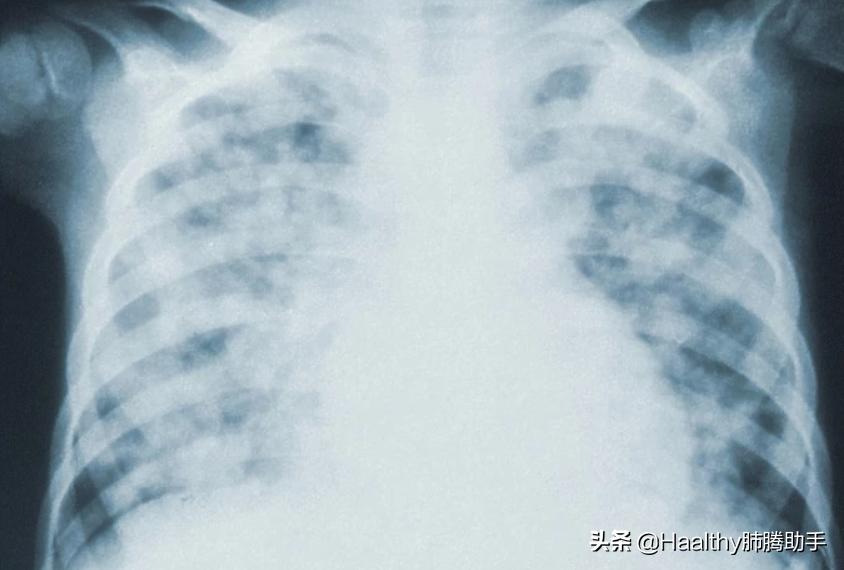

| 体检最常见的项目——X线胸片

在国内的大多数体检里,胸片X线检查可以说是最为常见。因为价格便宜,辐射也相对较弱,非常适合年轻、相对身体比较健康的人群,每年做一次常规的体检。

但是X线胸片也有很一个不可忽视的问题——较小的肺部病灶很难发现,肺部的小结节或微小结节很容易被肋骨、膈肌、纵隔组织器官等遮挡,容易遗漏了大部分直径小于2cm的病灶。据统计,约有22%-63%的肺癌病灶容易被漏诊。有些患者在临床确诊肺癌时就已经是中/晚期,失去了外科手术根治的最佳时机。

所以如果是肺癌高危人群,体检做了X线胸片,并不保险!不推荐将X线胸片作为肺癌筛查工具,体检照胸片来排查肺癌也是无效的。